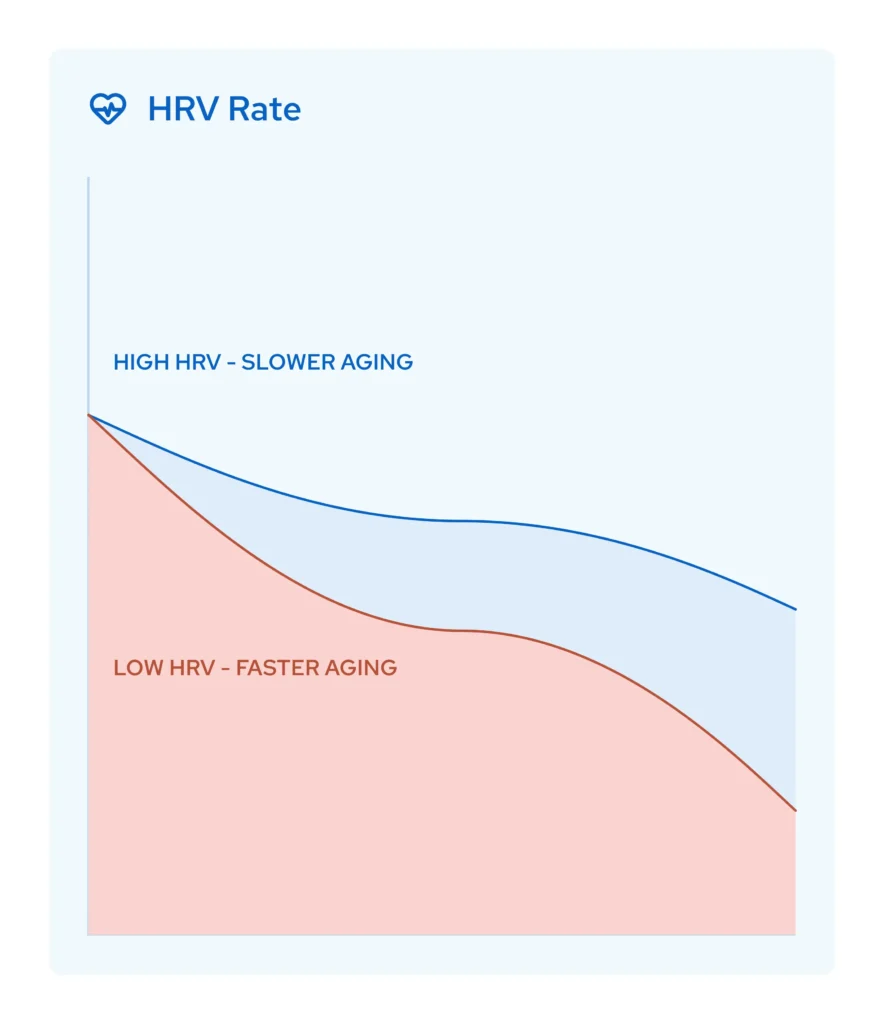

Higher HRV = Slower Biological Aging

Heart Rate Variability (HRV) is one of the most reliable biomarkers of biological age. High HRV means your body adapts well to stress and recovers efficiently. Low HRV? Your system is rigid, inflamed, and aging faster.

In a scientific study, Nurosym increased HRV by 18% and increased by 61% the vagal parasympathetic activity to placebo (PLOS ONE journals) in studies.

That’s not just a number, it’s your body regaining the flexibility and resilience associated with youth.

Track it.

Measure it.

And watch your biological age improve.